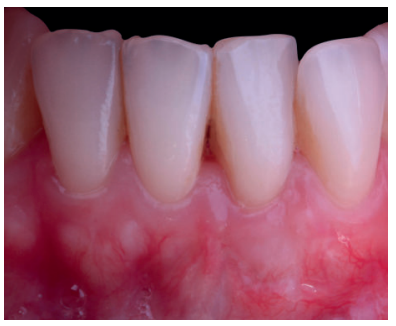

Mujer de 23 años que acudió a nuestra consulta debido a la presencia de múltiples recesiones gingivales desde el diente 32 al 42. La paciente refiere que nota sus dientes más largos, no presenta problemas de hipersensibilidad y había terminado el tratamiento ortodóncico hacía 1 año. La historia médica de la paciente no mostraba datos relevantes. No informó de alergias y no tomaba medicación de ningún tipo. El examen clínico periodontal reveló múltiples recesiones gingivales vestibulares que afectaban a los dientes 32, 31, 41 y 42 (Figura 9), con ausencia de tejido queratinizado apical a las recesiones de los dientes 31 y 32. Tras el estudio radiográfico (Figura 10) se observa pérdida ósea horizontal leve entre los incisivos inferiores (clase III de Miller y RT2 de Cairo).

El control a la semana (Figura 13) presentaba inflamación moderada y a las 2 semanas (Figura 14) se retiraron los puntos de sutura. La paciente acudió a los 4 meses (Figura 15) y al año (Figura 16) a visitas de revisión, donde se apreció una buena banda de tejido queratinizado y una pequeña cicatriz.